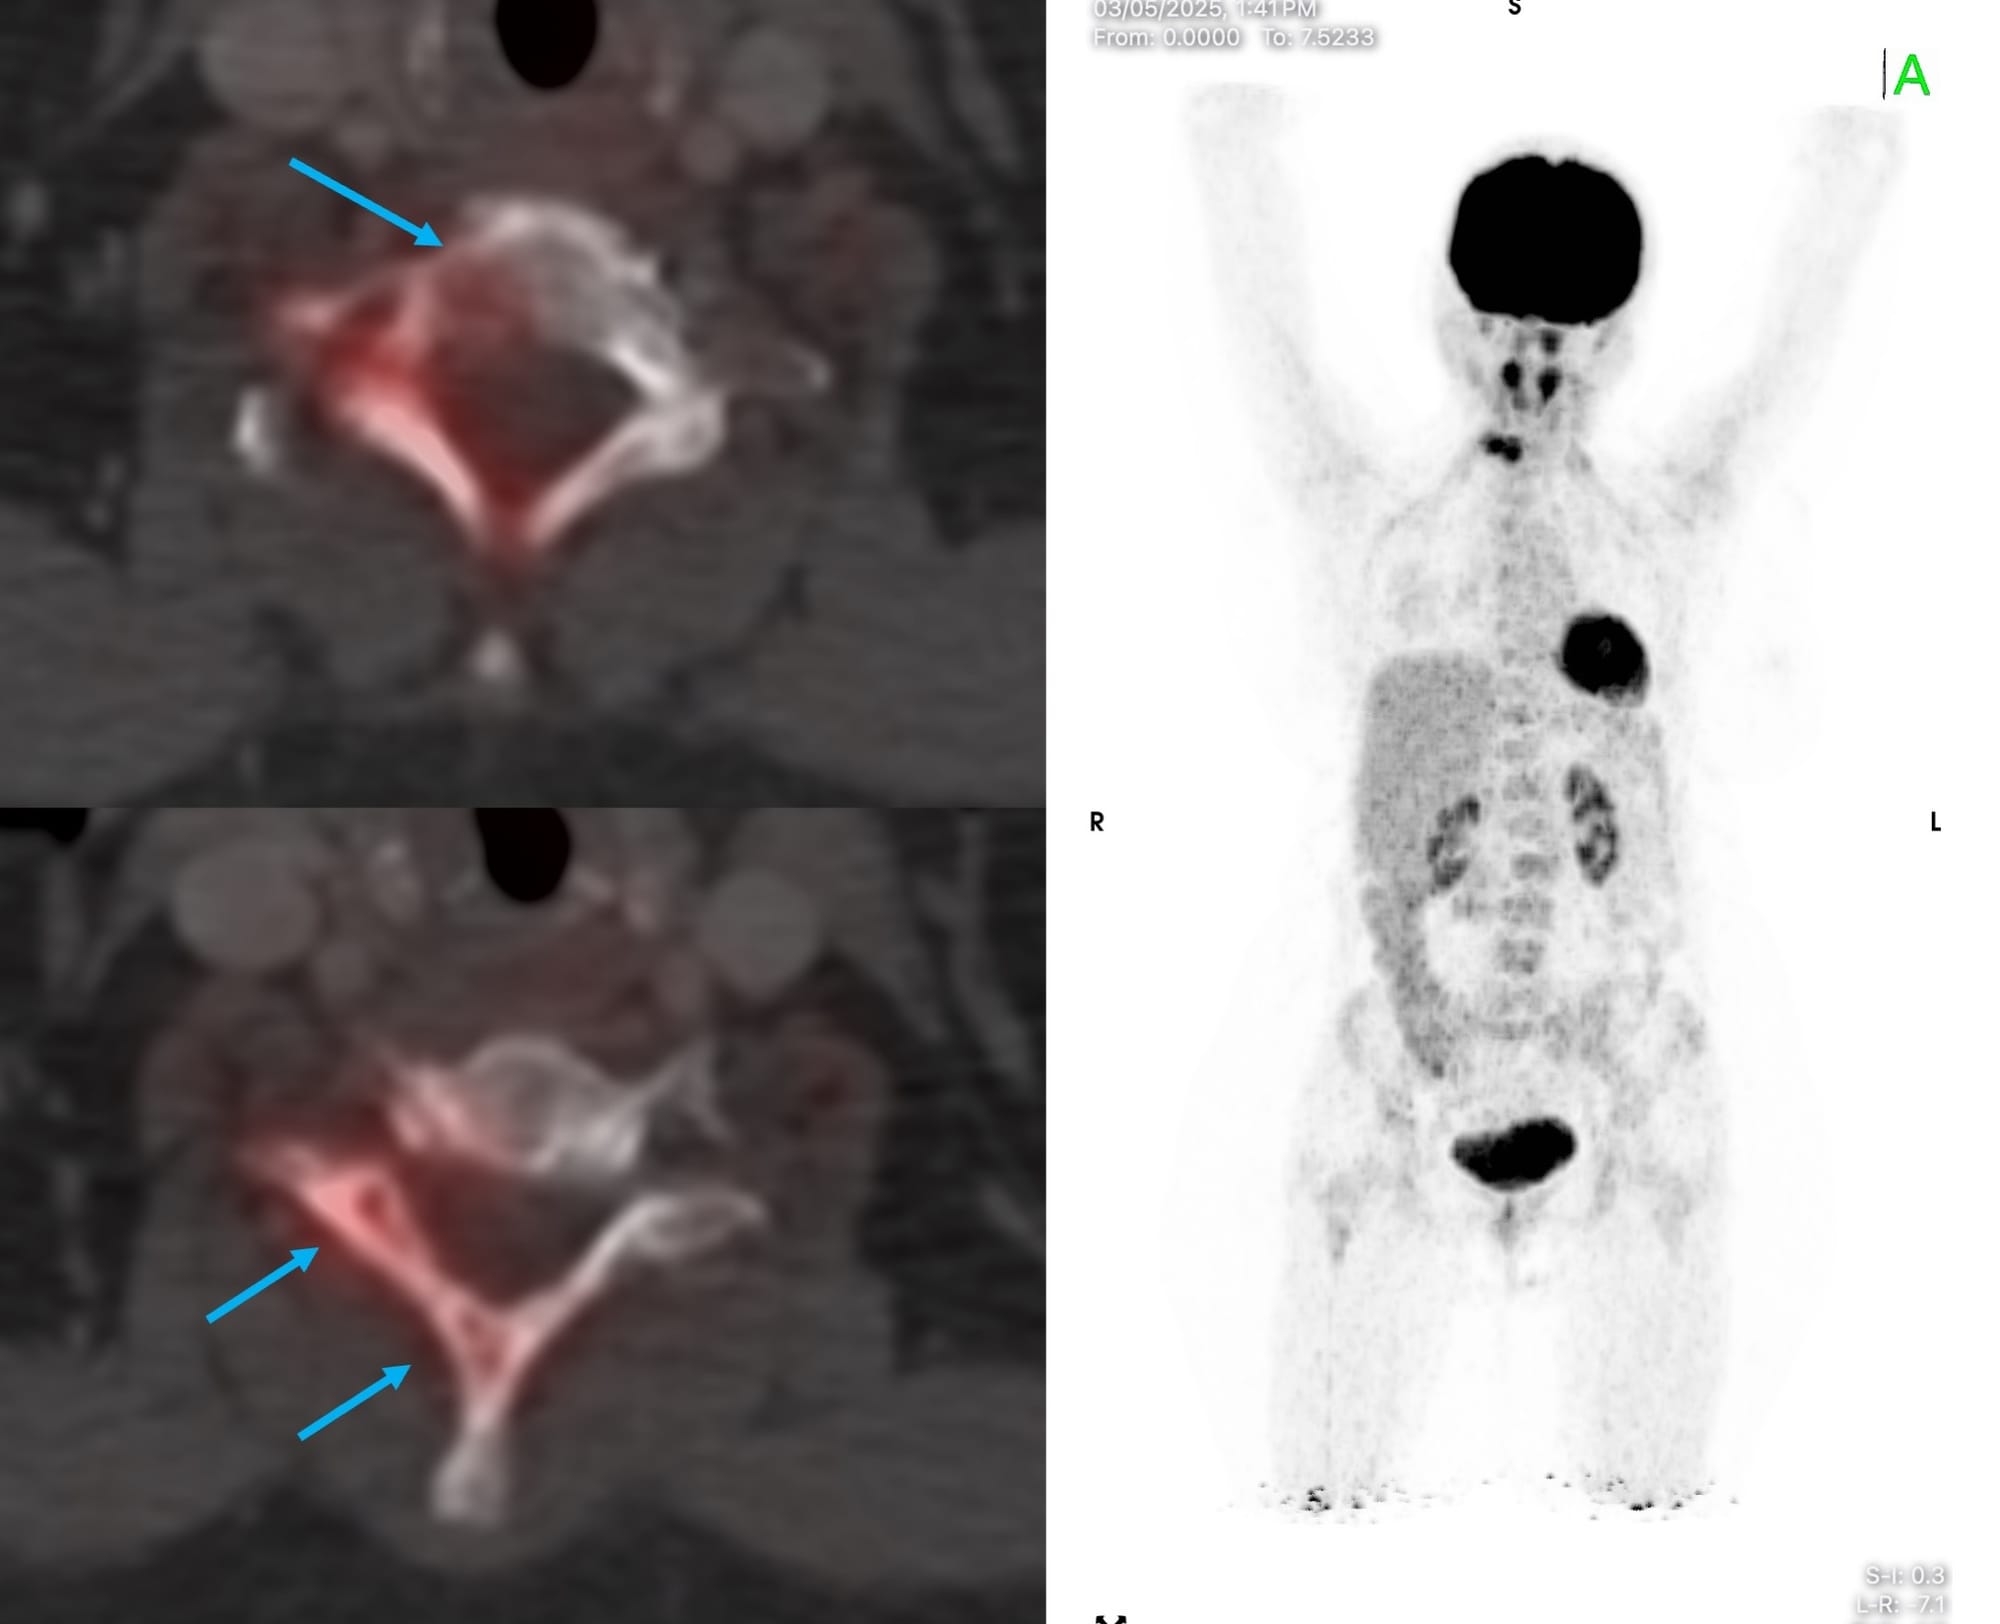

A 60-year old presented with a C7 body lesion on PET, confirmed on MRI.